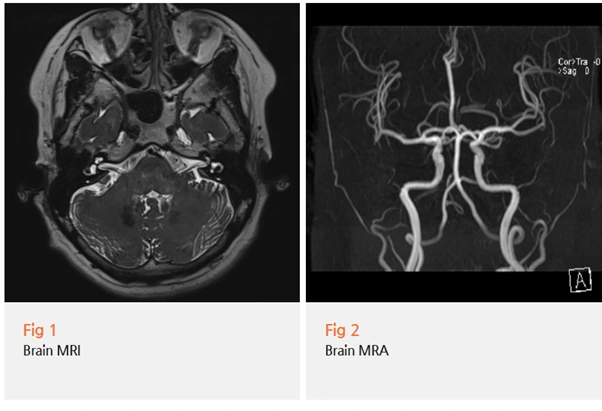

당일 뇌 MRI와 MRA, 근전도 검사를 진행했어요.

혹시 뇌혈관 이상이나 종양, 다발성 경화증 같은

심각한 문제가 숨어있는 건 아닌지 확인하는 과정이죠.

다행히 환자분은 뇌에 다른 문제는 없었어요.

하지만 여기서 끝이 아니었습니다.